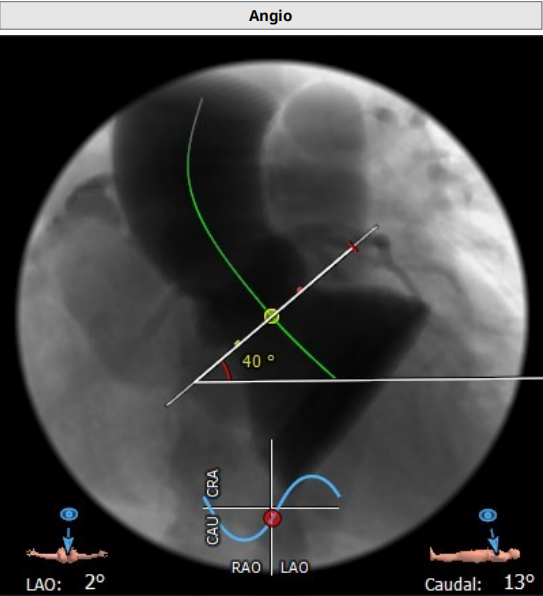

根部造影

Numed18mm球囊预扩,左右冠脉都有显影

植入L23瓣膜定位,进行高位释放